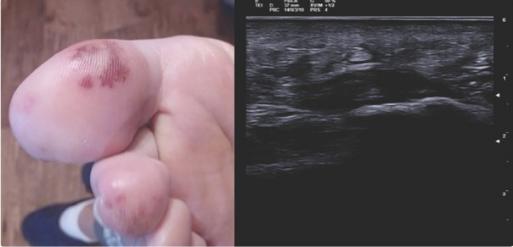

该物质的直径为4223毫米,属于AM(图2)。患者接受了切除肿块的手术。手术后,患者报告关节和皮肤症状完全消失,甲基强的松龙和MTX被停用。

图2、超声心动图显示AM几乎占据了整个左心房和二尖瓣。心房粘液瘤